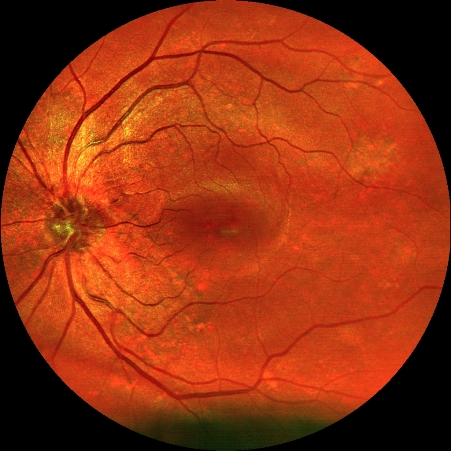

Hochauflösende Netzhautbilder für Ihre Gesundheit.

Das Easyscan SLO liefert in sekundenschnelle hochauflösende Bilder der Netzhäute. Das Easyscan ist so konstruiert, dass es selbst aus tiefer gelegenen Schichten der Netzhaut scharfe Bilder liefern kann.

Somit lassen sich Veränderung in der Netzhaut, selbst in den unteren Netzhautschichten, einfach erkennen. Bei Auffälligkeiten, seien Sie auch noch so winzig, können wir an den richtigen Augenarzt verweisen.